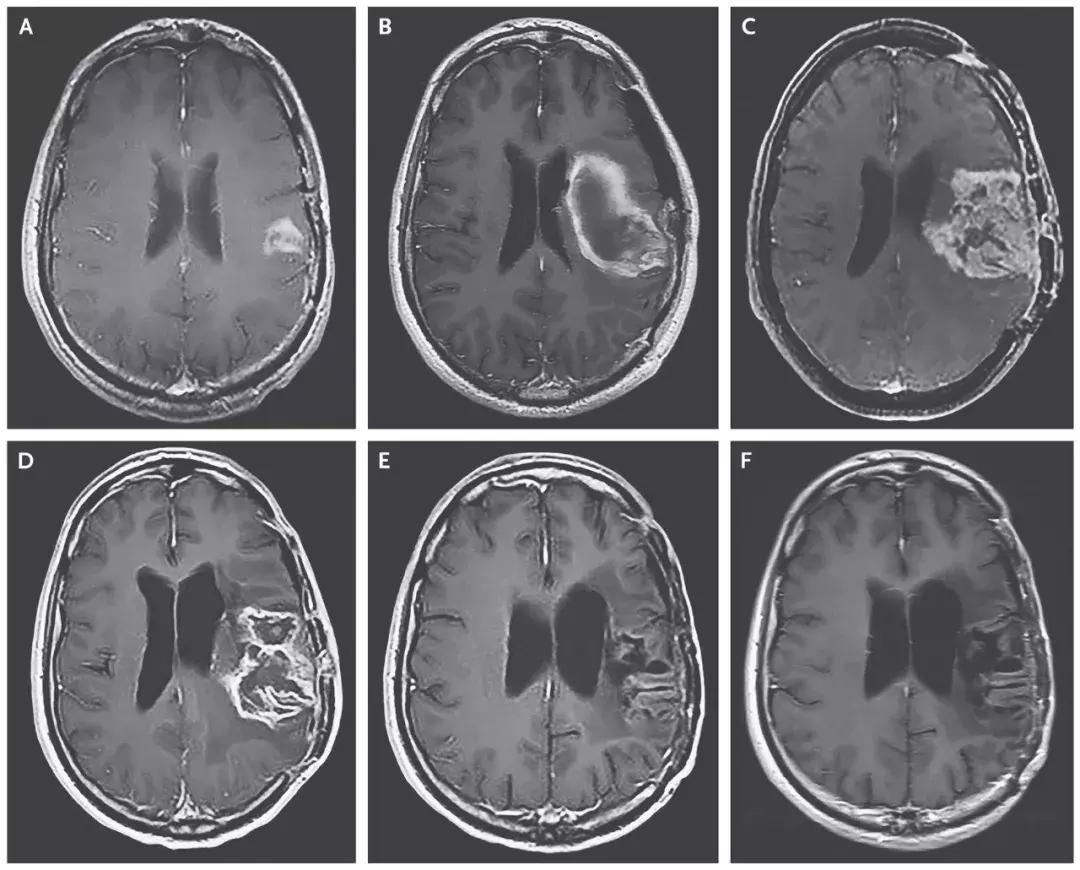

试验结果

- 治疗组的中位生存期是12.5个月,与11.3个月的历史数据相差无几;

- 在2年这个时间节点上,治疗组的生存率是21%,已经比历史数据(14%)高出50%;

- 在3年这个节点,治疗组的生存率同样为21%,而历史数据仅为4%。这意味,经过病毒的治疗后,这个生存率猛增5倍!

溶瘤病毒创造恶性脑瘤完全缓解的治疗奇迹!

截止2018年3月20日,8名患者对治疗产生治疗应答,2名患者的脑胶质瘤病灶完全消失,达到了完全缓解!

▲患者脑部肿瘤的缩小清晰可见(图片来源:《NEJM》)

这位患者,经过PVSRIPO溶瘤病毒治疗7个月后,病情复发后使用洛莫司汀治疗,经过12个月的洛莫司汀治疗后,病人的病灶完全消失并保持了20个月的无病状态,并且在PVSRIPO溶瘤病毒治疗发生出血后57.5个月仍然存活。